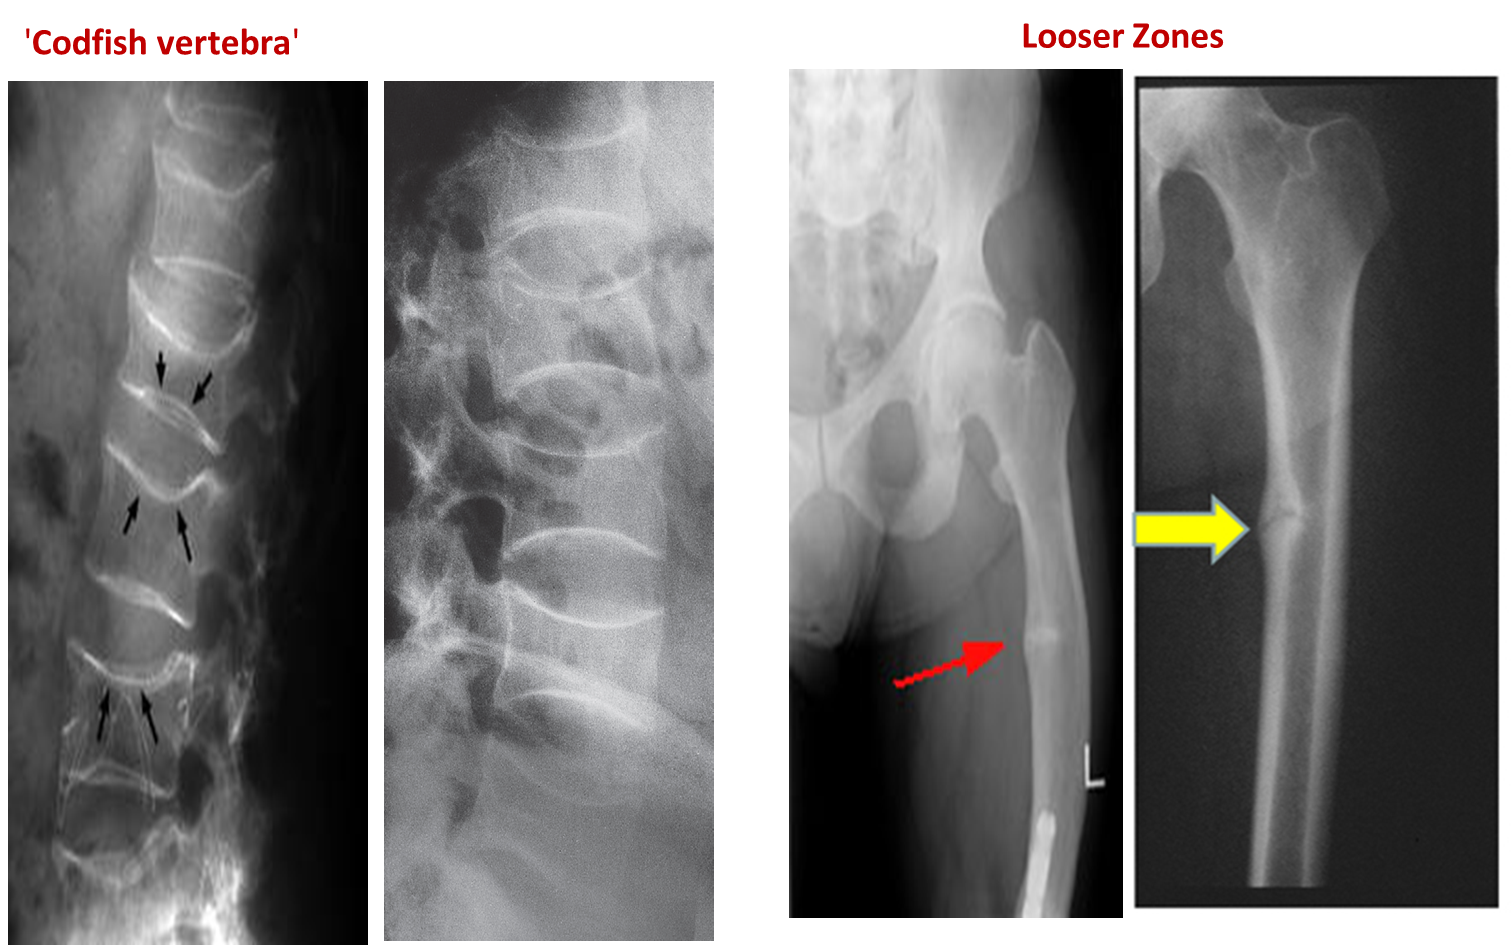

- Biconcave vertebrae & compression fractures

Characteristic Sign: Looser’s Zones

- Poorly healing stress fractures typically occurring at:

- Neck of femur

- Bone deformity. (vertebral bodies are biconcave, the femora may be bowed)

Vertebral bodies are biconcave

Looser’s zones Z are short lucent bands running through the cortex at right angles, usually going only part way across the bone